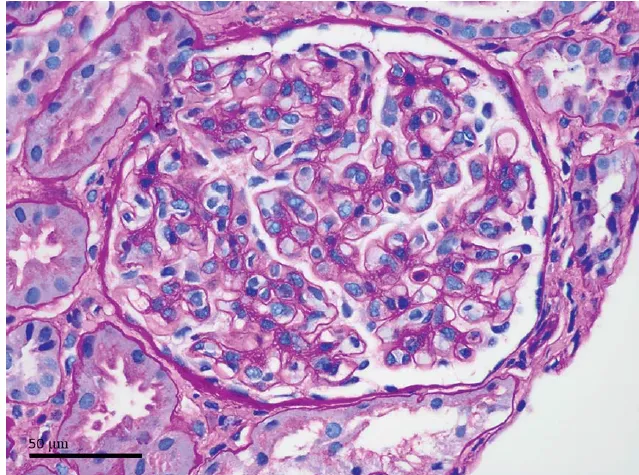

Uma causa incomum de hematúria glomerular intermitente!

Hematúria pós infecção, caso clínicos para auxiliar no entendimento de causas glomerulares comuns e raras...